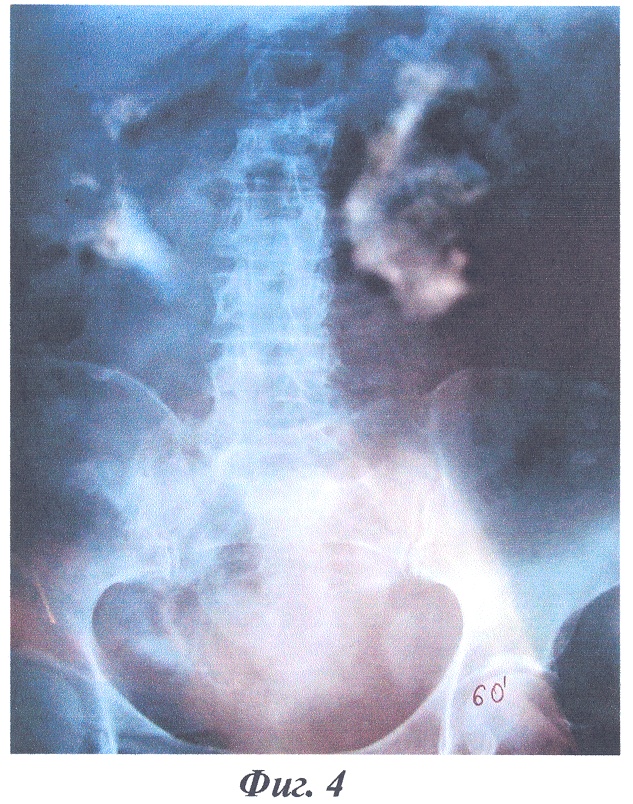

На фиг.4-6 изображены рентгенограммы клинического примера формирования накопительного мочевого резервуара предлагаемым способом.

В качестве примера приводится выписка из истории болезни больной Ж., 51 года, И.Б. №1111, которой по поводу постлучевой облитерации мочевого пузыря и уретры после лечения рака шейки матки T1N0M0 (фиг.4 – экскреторная урограмма до операции) 12.04.2004 г. была произведена операция (№169) с формированием “сухой” накопительной уростомы по предложенному способу. Послеоперационное течение гладкое, больная выписана в удовлетворительном состоянии на 29 сутки после операции.

Заключительный диагноз: постлучевая облитерация мочевого пузыря и уретры. Состояние после лечения рака шейки матки T1N0M0. Больная осмотрена через 2 года, данных за рецидив и метастазы не выявлено, при экскреторной урографии отмечается удовлетворительная функция почек, расширения чашечно-лоханочных систем и мочеточников нет (фиг.5, 6).